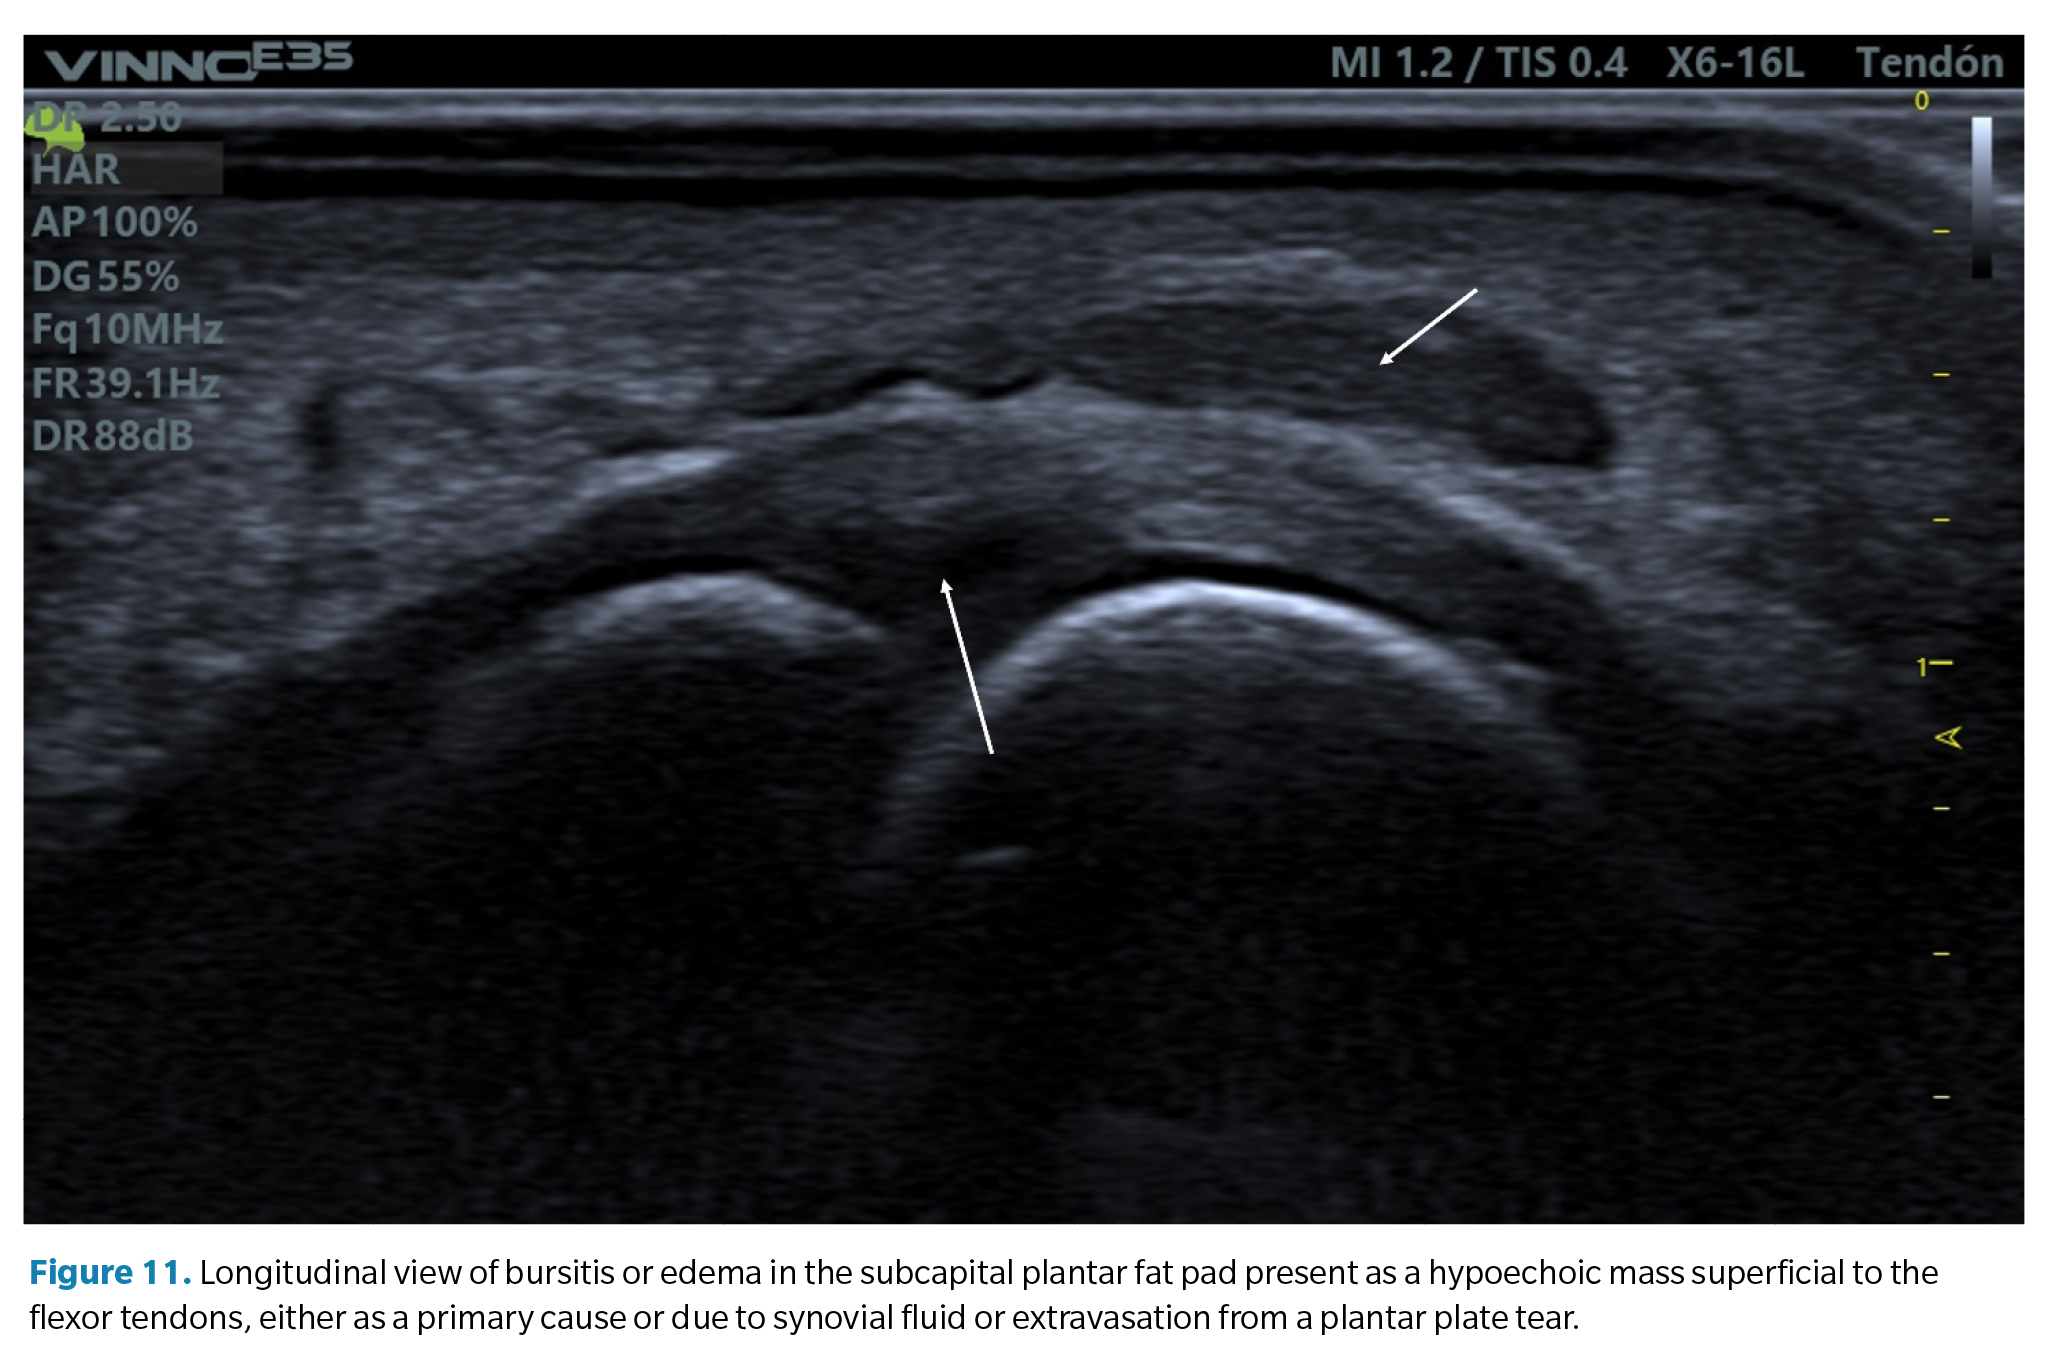

2. Bursitis of the plantar fat pad. In relation to the previous finding, some cases of plantar plate tears may also be accompanied by a hypoechoic infiltrate in the adjacent plantar fat pad. This may be a primary defect due to excessive compression of the fat (compression which is also part of the compressive injury etiology of the plate) or the result of a synovial fluid infiltrate due to capsular rupture extravasation as previously mentioned. It is common in these cases to detect a positive <

3. Echogenic enthesophytes in the proximal phalanx. In advanced stages, it is common to see marked irregularity of the plantar cortex of the proximal phalanx base and the presence of enthesophytes associated with plantar plate tears, similar to other ligaments where traction can cause avulsion of the bone tissue(43) (Figure 12).